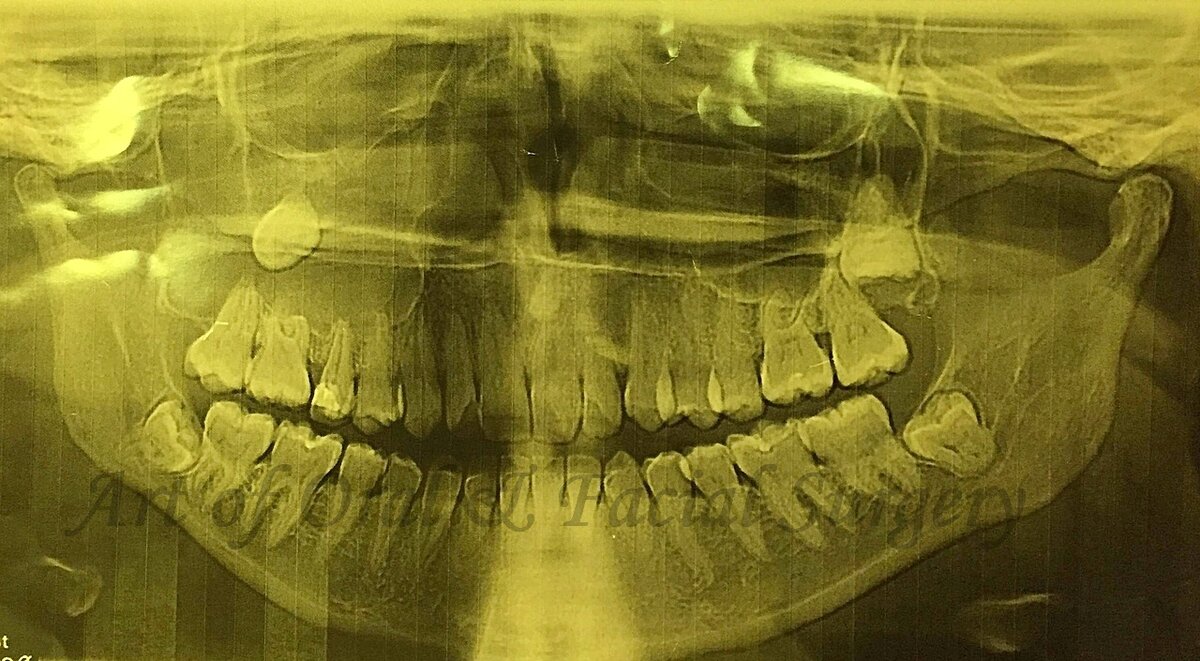

И вот красочный пример. Пациент, 46 лет, женщина. Из анамнеза известно, что месяц назад лечилась у стоматолога по поводу периостита верхней челюсти справа. Верхний зубной ряд интактный, одонтогенной причины выявлено не было. Для уточнения диагноза проведено ОПТГ.

ОПТГ

Обнаружен ретенированный 18 в области проекции правой гайморовой пазухи (на уровне скуло-альвеолярного гребня). Была направлена в стационар. При визуальном осмотре лицо симметрично. СОПР без видимых изменений. При пальпации в области бугра верхней челюсти справа определяется симптом «пергаментного хруста». 1.7,1.6 – интактные, подвижны 2 степени.